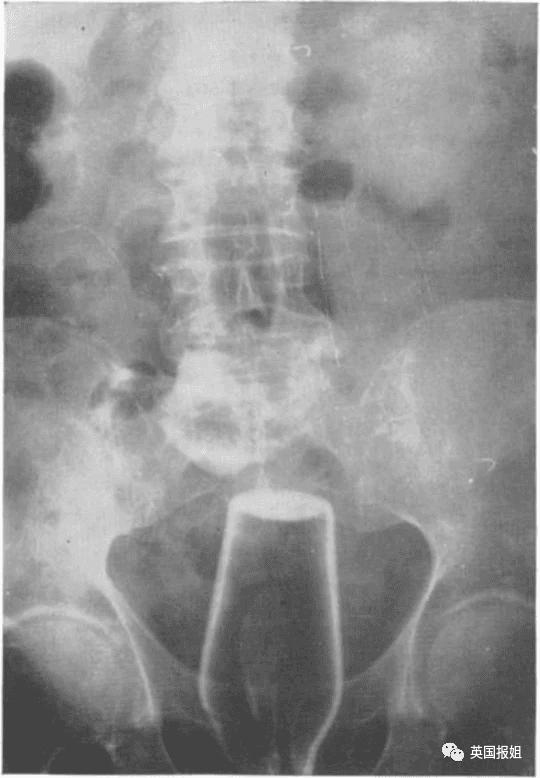

图中的患者是一名72岁的老翁,他自称在上厕所时不慎跌倒在了一个倒着的酒瓶上: